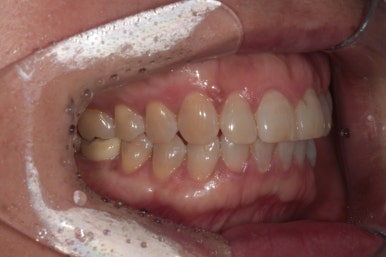

정면에서 본 사진입니다.

잘 모르실 수도 있겠지만, 잇몸이 염증이 생겨 치주염으로 인해 빨갛게 변하신 것을 보실 수 있어요.

즉, 잇몸질환-만성치주염을 갖고 계신 상태였죠.

위 앞니 (중절치)는 치아 사이 틈을 메우기 위해 예전에 레진치료를 받으신 상태였는데, 치료받으신지 오래되어 레진 충전물의 색이 변하고 어색한 모양을 띄고 있습니다.